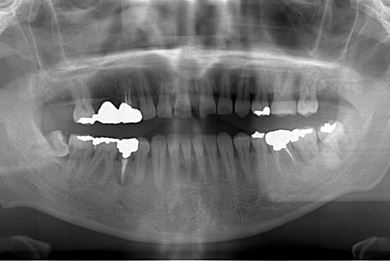

性別/年齢 男性 / 39歳

主訴 前歯のすき間を治したい。

治療方針 上顎前歯をオールセラミッククラウンにて審美的回復を行う。

治療内容 CAD/CAMオールセラミッククラウン2本

治療前

• 治療前